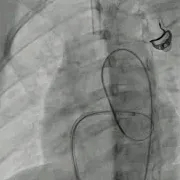

牵拉成型线锁定后,分流消失,主动脉瓣反流消失。

封堵器锁定后呈“蝴蝶状”明显盘状形态,室水平分流完全消失,主动脉瓣反流消失。

锁定后牵拉及释放

牵拉试验,封堵器稳定无移位,释放封堵器后超声下确认无残余分流,无主动脉瓣反流,三尖瓣反流同术前无增加。

大动脉短轴切面,封堵器释放后双盘紧贴间隔,呈现完美“工字形蝴蝶形”,顺应VSD形态及瓣膜形态。

MemoSorb全降解VSD封堵器展现了极佳的顺应性,在通过长隧道、小出口的VSD后,能顺利从“长哑铃”形态展开并固定为贴壁良好的“蝴蝶”形态。术后即刻超声评估显示,伞盘封堵完全,对相邻瓣膜无任何影响,主动脉瓣及三尖瓣均未出现反流。